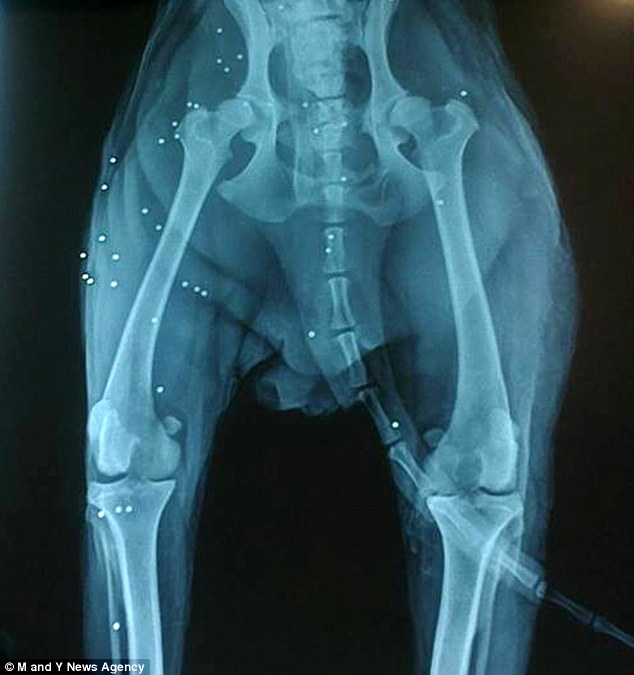

O cão levou 38 tiros de chumbinho e foi jogado em um fosso, onde apenas sua cabeça ficava para fora d’água.